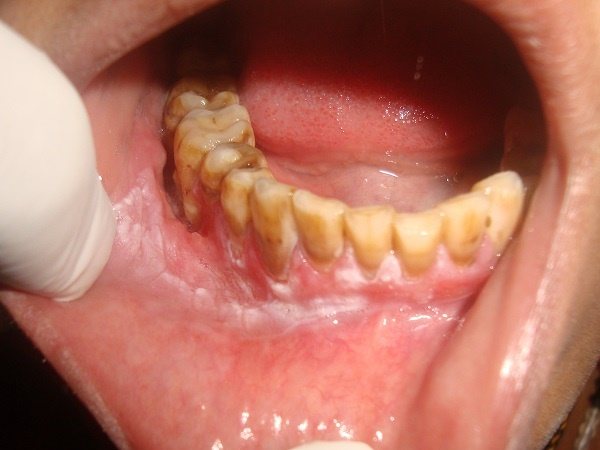

Его могут провоцировать следующие факторы:

- выступающая или свисающая над десной пломба;

- массивные отложения камня;

- заостренные края разрушенных единиц;

- плохая гигиена;